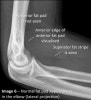

Anterior fat pad is located in the coronoid fossa. A narrow anterior fat pad is a normal finding on the lateral view.

The posterior fat pad is located in the olecranon fossa on the lateral view. It should not be visible under normal circumstances.